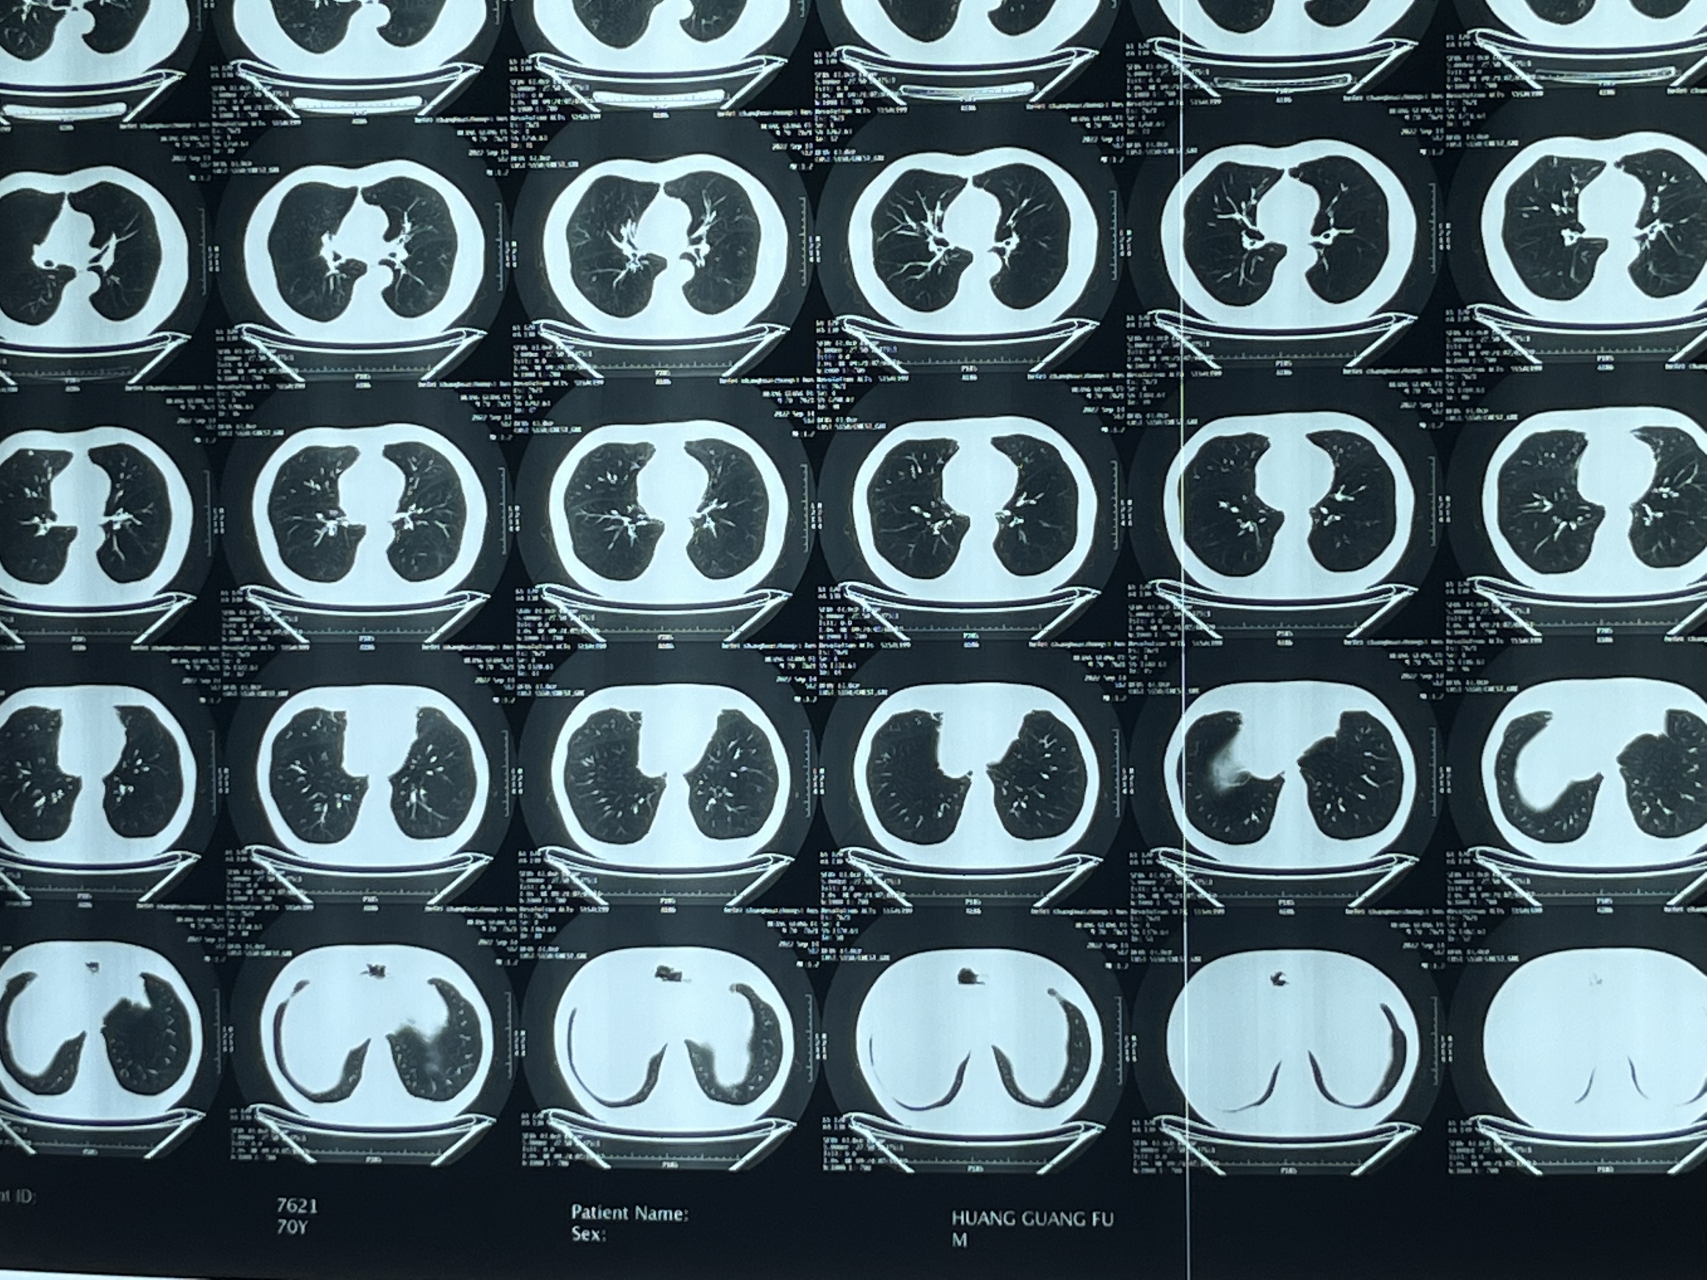

65岁双肺多发磨玻璃结节介于原位到微浸润腺癌之,别急,可以等等